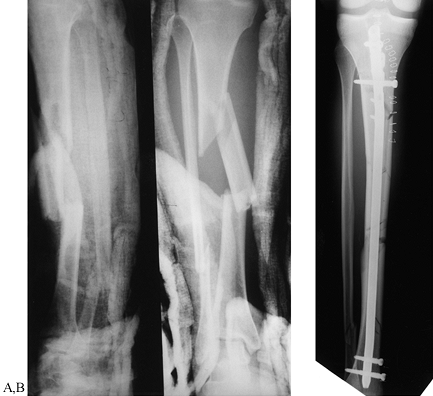

Figure 24.5. Radiographic examples of the four grades of tibial fracture severity. A: Minor severity: spiral fracture caused by a simple slip and fall. B: Moderate severity: transverse fracture in a pedestrian struck by slowly moving vehicle. C: Major severity: comminuted fracture with tibial-fibular diastasis caused by a high-velocity motorcycle crash. D: Major severity: near amputation caused by a high-speed motorcycle accident; with segmental bone loss.